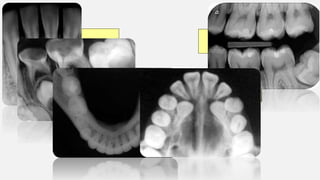

TIPOS DE RADIOGRAFÍAS INTRAORALES

TIPOS DE RADIOGRAFÍASINTRAORALES Interproximal o aleta mordible Oclusales Periapicales o dentoalveolar